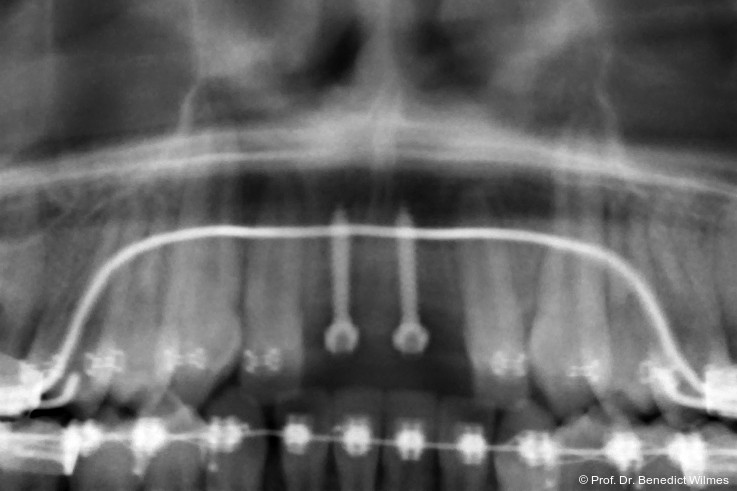

Ein 14-jähriger Patient wurde bei Aplasie der beiden oberen seitlichen Schneidezähne mit dem Ziel der beidseitigen Lückenöffnung kieferorthopädisch therapiert (Abb. 1a+b). Zum Ende der kieferorthopädischen Behandlung wurden zwei Miniimplantate in Regio 2er als temporärer Zahnersatz inseriert (Benefit System, PSM, 2 x 13 mm, Abb. 2a+b). Nach Abdrucknahme wurden Kronen auf den Peek-Abutments modelliert und diese mit Kunststoff auf die Abutments geklebt (Abb. 3a–d). In den Abbildungen 3 und 4 sind die klinischen und röntgenologischen Nachkontrollen innerhalb der nächsten achteinhalb Jahre dokumentiert. Man erkennt einen sowohl in der Höhe als auch in bukkopalatinalen Breite verbleibenden gesunden Knochen ohne Anzeichen einer Atrophie. Im Alter von 23 Jahren wurden die definitiven Implantate ohne die Notwendigkeit einer Augmentation eingesetzt (Abb. 5) und nach Einheilung prothetisch versorgt (Abb. 6a–e und Abb. 7a–c).